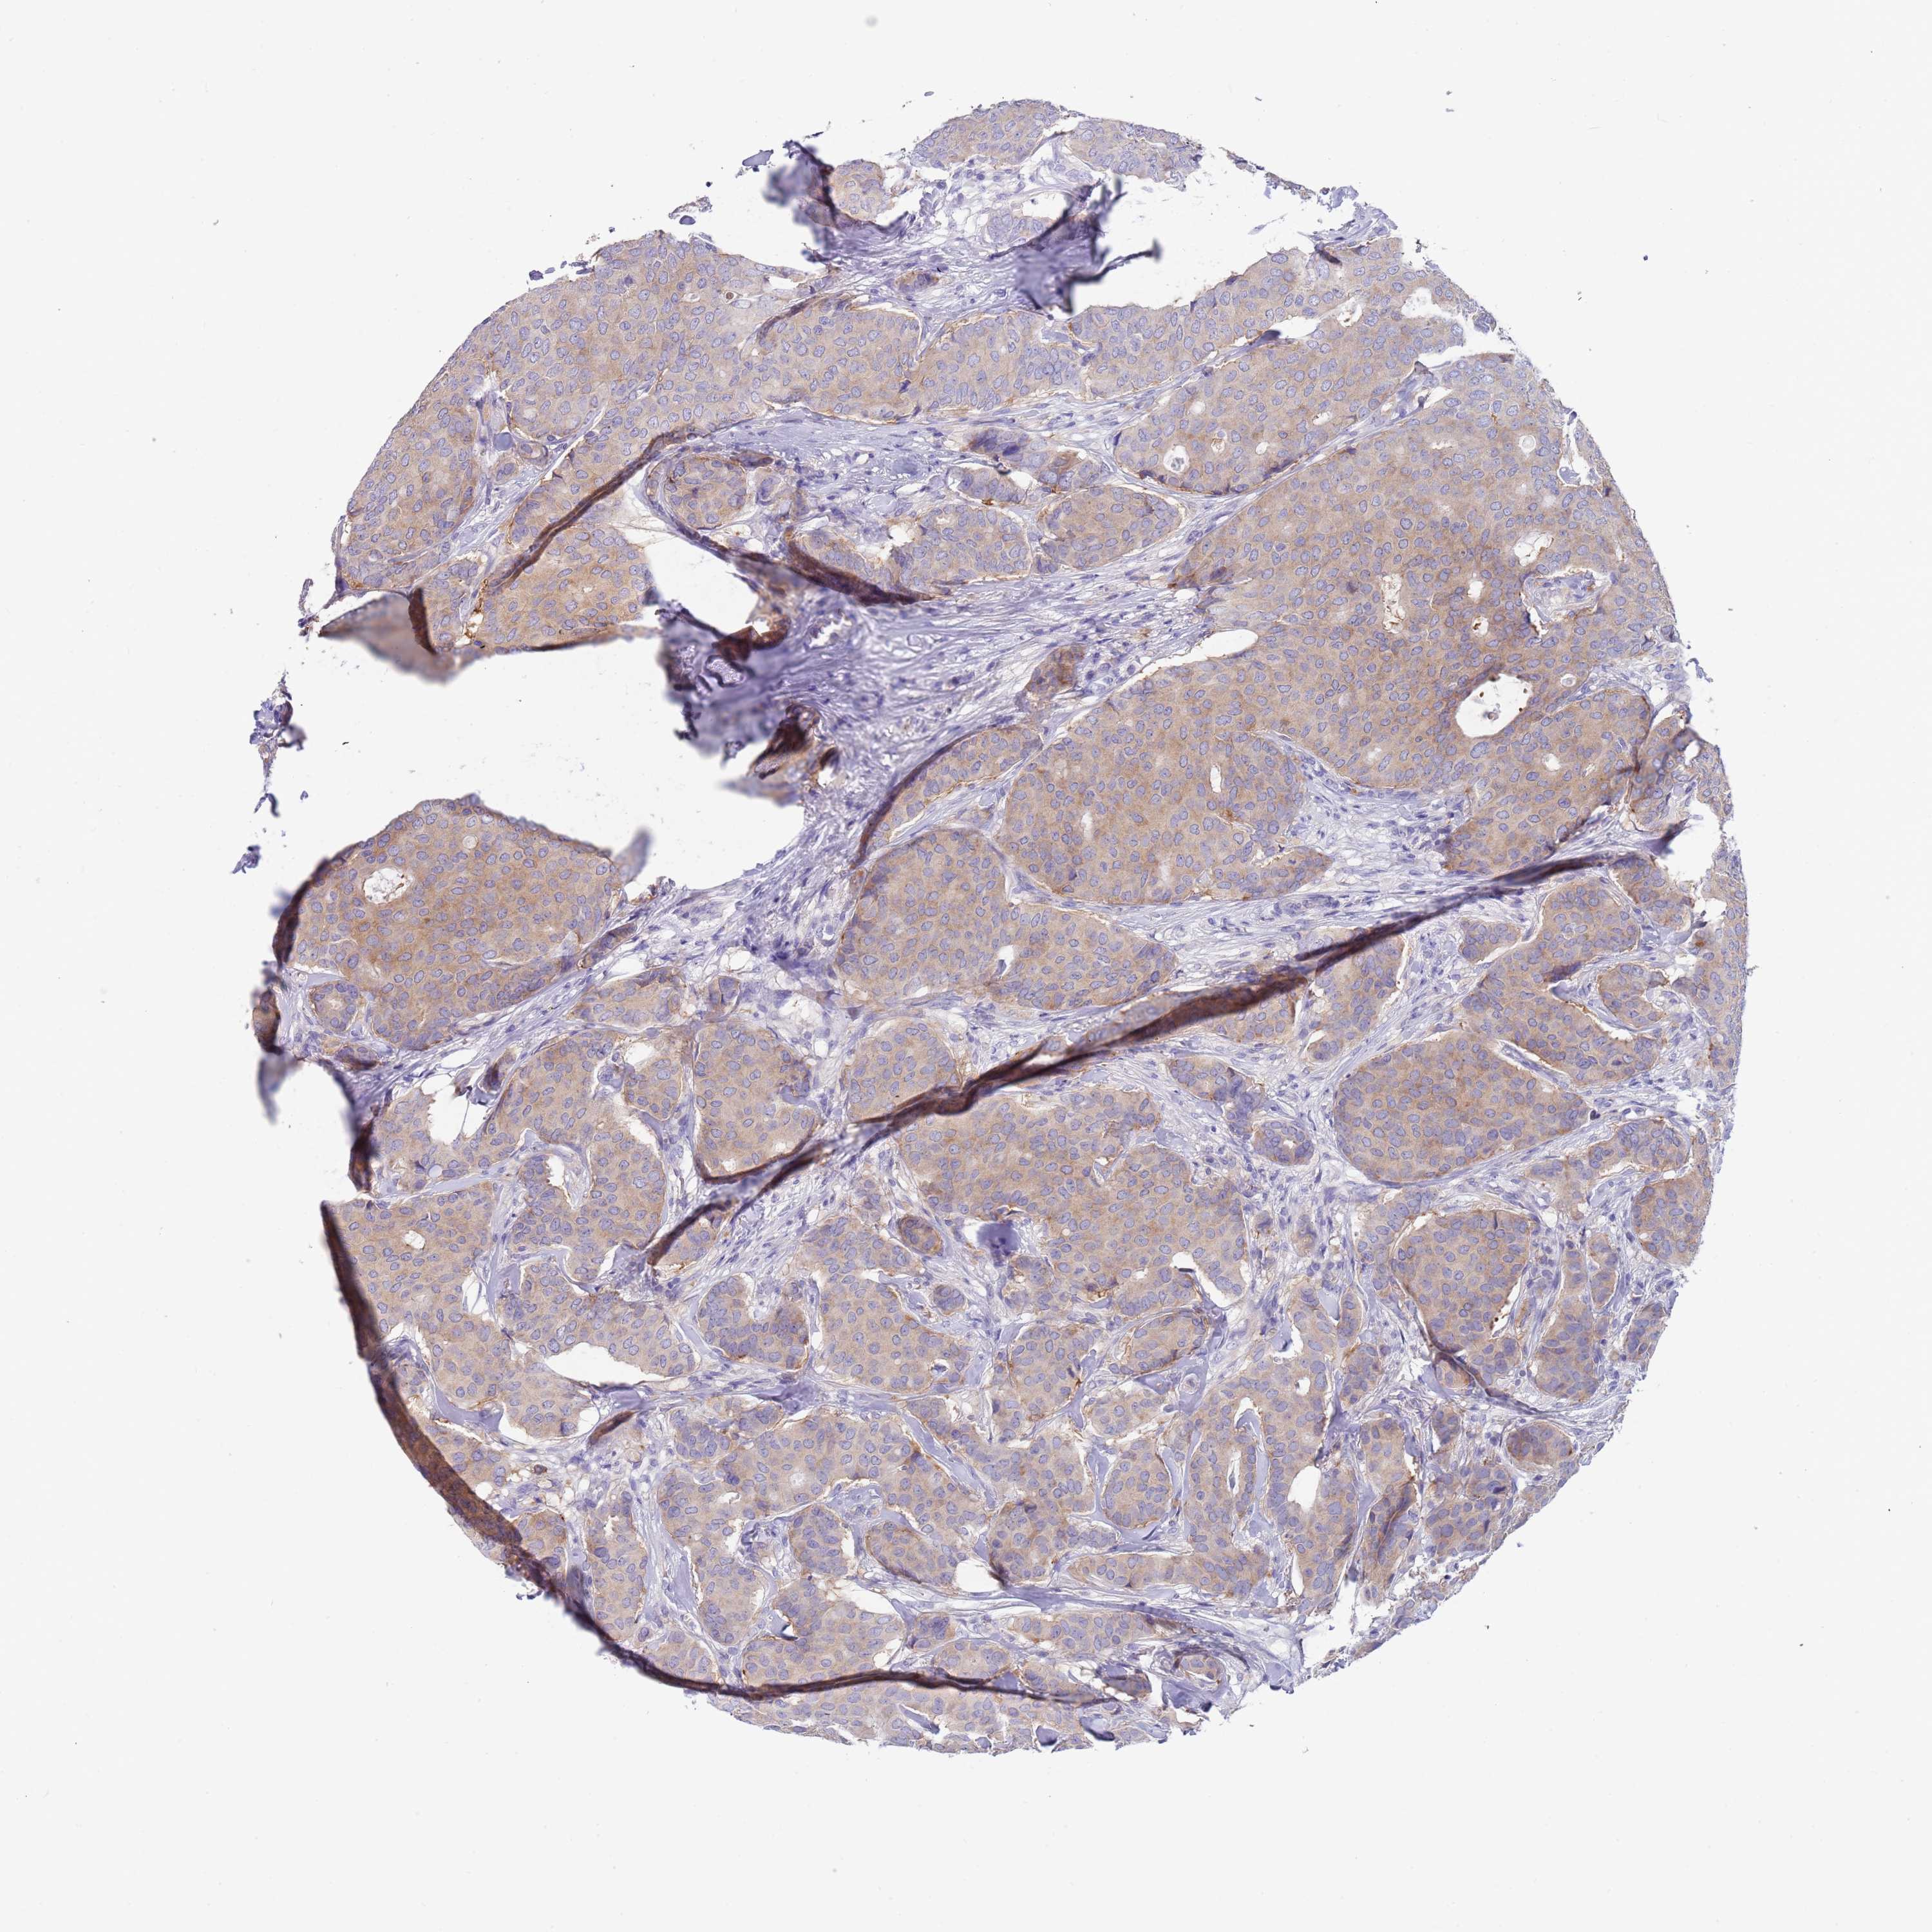

CANCER BREAST CANCER Show tissue menu

BRCA TCGA BRCA VALIDATION PROTEIN EXPRESSION